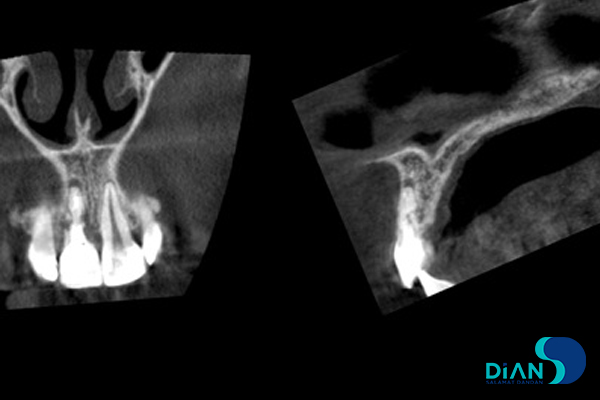

The CBCT showed fracture of 11 tooth root as well as a significant replacement of construction in relation to other tooth alveolar socket.

In this situation, there are no options for tooth restoration in terms of unreliable result. So the patient rejected such tactics. It was decided to do immediate implantation after tooth extraction. The dentist made treatment plan and implants position according to the size of CBCT results.